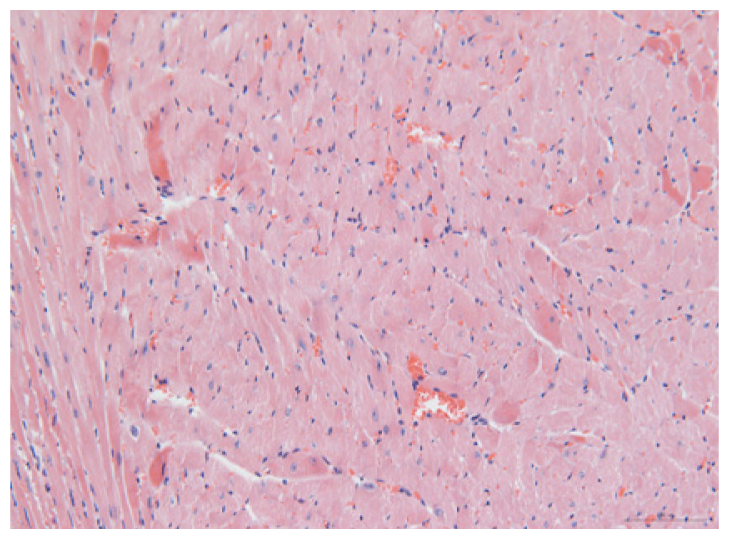

2.1.6. CoPP Treatment Diminished Infarct and Peri-Infarct Area in ISHR Model

2.1.7. CoPP Treatment Inhibited Ventricular Remodeling of Post-Infarction in SHR

| Groups | Masson (macroscopic) | Masson (×200) | Infarct area (HE ×200) | Peri-infarct area (HE ×200) |

|---|---|---|---|---|

| WN | ![]() | ![]() | ![]() | |

| SMN | ![]() | ![]() | ![]() | ![]() |

| SMC | ![]() | ![]() | ![]() | ![]() |

| SMS | ![]() | ![]() | ![]() | ![]() |